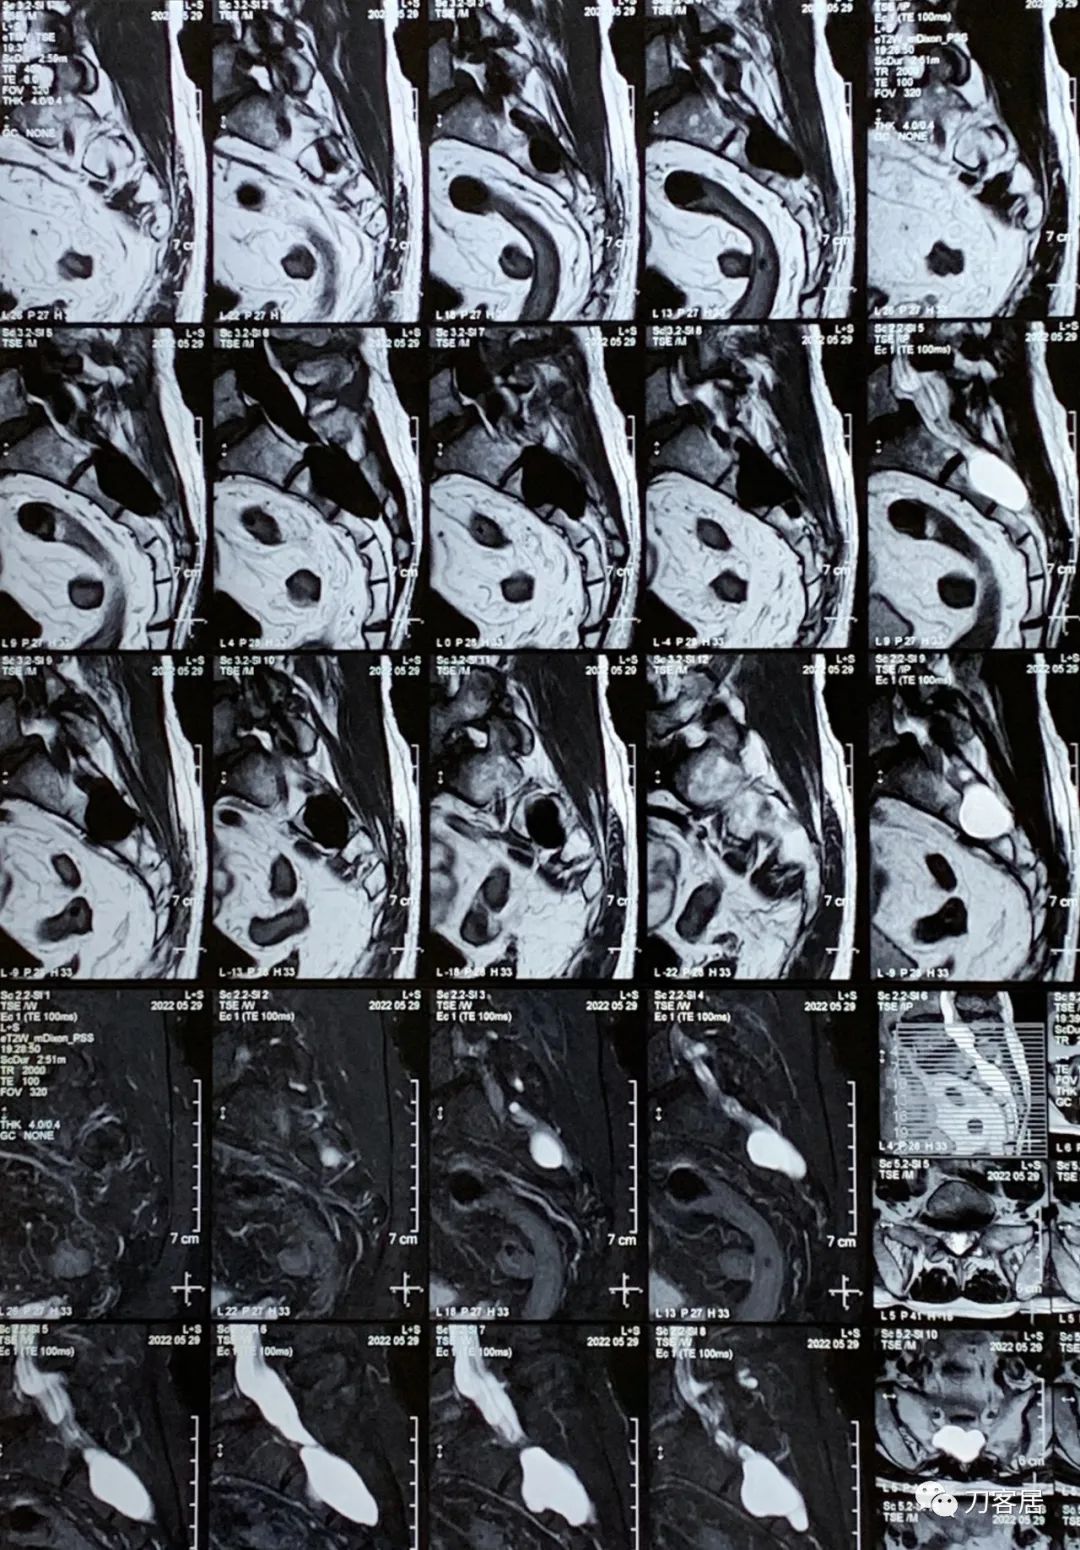

患者返回西安后,术后患者的症状并无明显的改善,2022年5月29日到西安北方医院神经内科就诊,查脑部以及脑血管造影,未发现问题,腰骶椎磁共振检查,显示骶管囊肿依旧。

图14. 20220529西安北方医院骶椎MRI